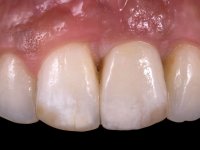

O ajuste final da cor/shade da restauração directamente em boca têm grande importância no sucesso do tratamento. Qualquer alteração necessária pode ser realizada nesta fase. As tonalidades de dentina e incisais foram aplicadas em conjunto de acordo com o esquema de estratificação visando a sua caracterização individualizada, mas ainda não foi aplicada a camada de superfície que dá translucidez á restauração. Este facto, permite que possíveis deficiências na cor/shade possam ser corrigidas removendo porções de cerâmica que apresentem tonalidades indesejadas. O brilho/brightness da primeira camada não deve ser muito baixo, porque pode fazer com que a restauração apresente um aspecto acinzentado. Esta situação pode ser contornada utilizando uma pastilha um pouco mais clara do que a cor/shade que se pretende para o resultado final.

Neste caso a paciente foi vista no laboratório, o que tornou possível estabelecer o correcto nível de saturação da cor e brilho. Quando a construção da cerâmica estava optimamente ajustada em termos de cor/shade, os componentes da translucidez puderam ser finalmente acrescentados. Nesta fase foi também completada a anatomia e a textura superficial de acordo com a informação dada pelos detalhes reproduzidos no modelo. A caracterização com tonalidades e essências no ciclo final de cozedura é fundamental, permitindo um ajuste fino da caracterização.

A confecção de um coto de óxido de zircónio com uma coroa de cerâmica vítrea prensada de dissilicato de lítio mimetizou perfeitamente os dentes vizinhos.